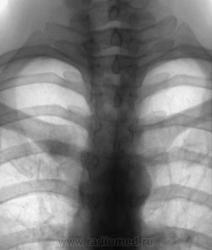

Молодая женшина. 31 год. На плановой цифровой ФГ выявлено неясного генеза изменения. При контрольной прицельной рентгенографии - в правой ключице. Чем Вы можете обьяснить локальный остеосклероз грудинного конца ключицы? При изучении анамнеза - отмечает боль в ключице (соответствует выявленым изменениям), которая распространяется на плечо, надплечье, спину и ...даже в правую руку... Рекомендована КТ.

Виктор Григорьевич, очень тщательно смотришь, забросаешь себя контролями, не отобьешся. Склероз для кости - это не плохо, это не деструкция... Нужно посмотреть, что там в шее (по симптомокомплексу)

А может это синдром Титце...

Была и у меня схожая мысль...но сбивает с толку остеосклероз....

Также нельзя исключить костную мозоль на почве перелома ребра, болезненные метастазы злокачественных опухолей или первичную опухоль ребра. В клинике крови есть какие-либо изменения?